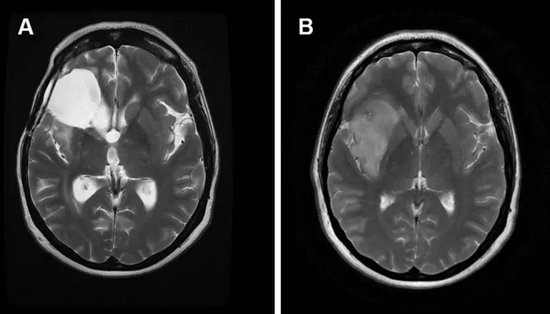

除功能性头痛,卵圆孔未闭更大的潜在风险,是导致矛盾栓塞。即来自下肢深静脉或右心系统的血栓,通过卵圆孔进入左心系统,继而导致外周动脉尤其是脑血管栓塞。

死亡原因分析:

建安二十五年正月(公元 220 年),曹操长途跋涉,班师回朝。因长时间鞍马劳顿,深静脉血栓形成并脱落,通过开放的卵圆孔暗度陈仓,最终栓塞在大脑中动脉,随即病逝,享年 66 岁。